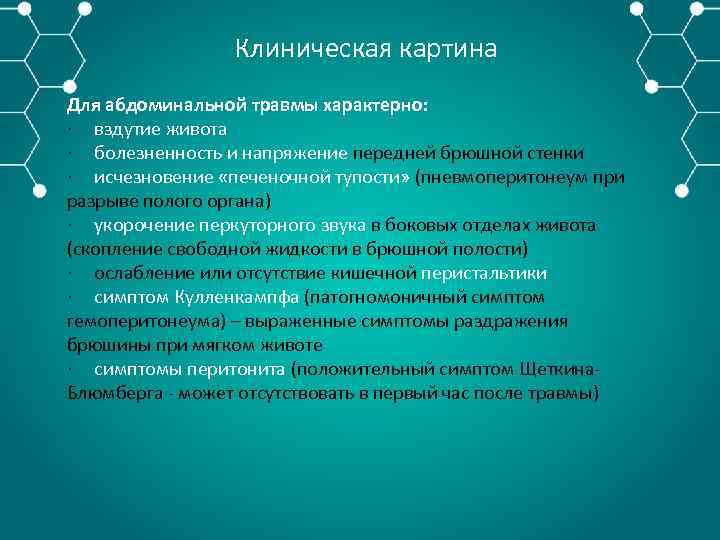

Клиническая картина Для абдоминальной травмы характерно: · вздутие живота · болезненность и напряжение передней брюшной стенки · исчезновение «печеночной тупости» (пневмоперитонеум при разрыве полого органа) · укорочение перкуторного звука в боковых отделах живота (скопление свободной жидкости в брюшной полости) · ослабление или отсутствие кишечной перистальтики · симптом Кулленкампфа (патогномоничный симптом гемоперитонеума) – выраженные симптомы раздражения брюшины при мягком животе · симптомы перитонита (положительный симптом Щеткина Блюмберга может отсутствовать в первый час после травмы)